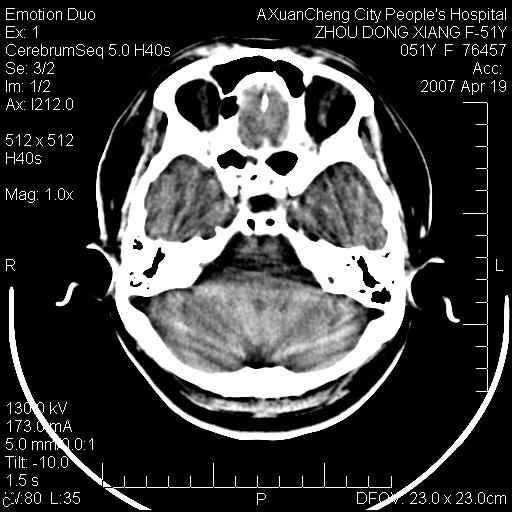

这个患者是外科手术后,第一次ct检查显示颅内多发积气和椎管内积气

现在复查后颅内这样怎么会事

第一次ct检查显示颅内多发积气和椎管内积气,现双侧基底节区及四叠体池周围多发斑片状低密度影,灰白质分界清楚,侧脑室前角变窄,患者为胆囊手术后,现在患者好象已经多脏器衰竭表现了,考虑:1. 血源性脑脓肿脑炎期改变?2. 缺血缺氧性改变?

第一次ct检查显示颅内多发积气和椎管内积气,现双侧基底节区及四叠体池周围多发斑片状低密度影,灰白质分界清楚,侧脑室前角变窄,患者为胆囊手术后,现在患者好象已经多脏器衰竭表现了,考虑:1. 血源性脑脓肿脑炎期改变?2. 缺血缺氧性改变?--支持